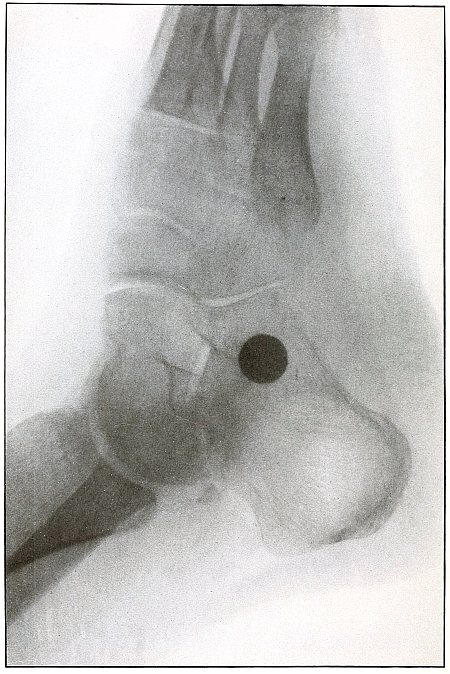

Rifle—Plate 59.

Gunshot Wound of the Left Knee-Joint,

with Lodgment of the Missile in the Joint.

The course of the bullet was transverse, entering the capsule posterior to the patella without injury to the bone.

As its shadow projection is almost circular, the bullet must be standing almost on its end pointing toward the plate with its long axis almost parallel to the line of projection.

As the fibular side of the leg lay next to the plate and as the only slightly enlarged shadow of the bullet indicates it to be near the plate, its position is in the joint near the fibular side.

As the bullet is undeformed and its penetrating power very slight, its velocity was that of extreme range.

The emergency treatment, is, of course, a simple antiseptic dressing with the leg held in the most comfortable position by muscular action.

The subsequent treatment is removal of the bullet when proper surgical conditions obtain. [Pg 130]